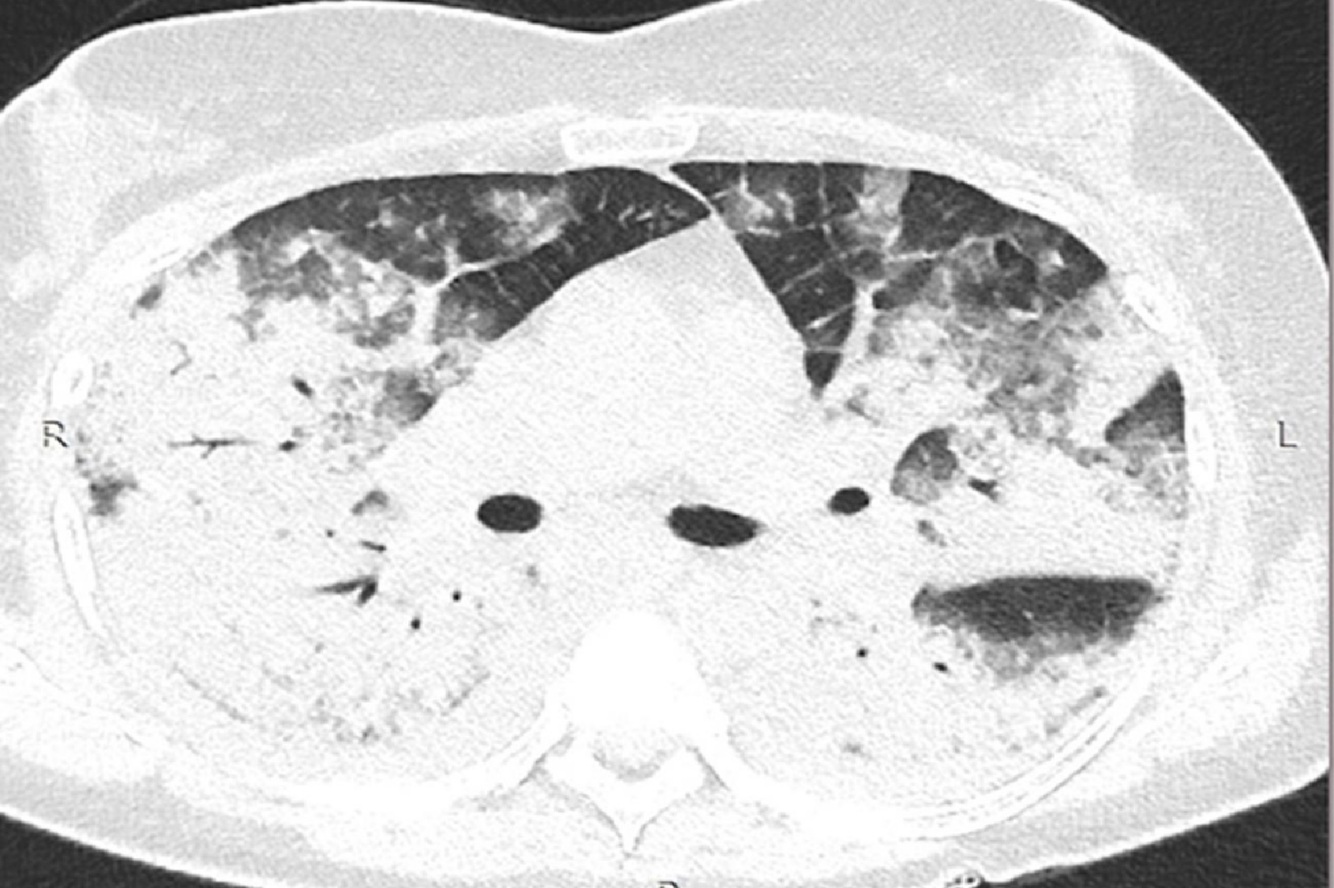

Infiltrado bilateral difuso na SARA: